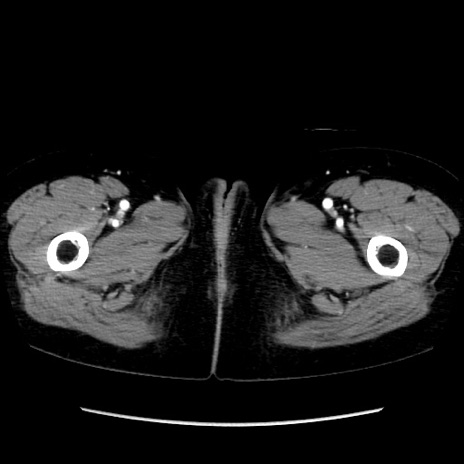

症例32(横断像)

【症例】40歳代 女性

【主訴】上腹部痛、嘔気・嘔吐

【現病歴】約9時間前頃から急に上腹部痛、嘔気、嘔吐が出現。改善しないため救急要請。

【既往歴】子宮頚癌(広汎子宮全摘術、放射線療法)、腸閉塞

【身体所見】腹部:平坦、軟、腸雑音亢進、上腹部を中心に腹部全体に圧痛あり。

【データ】WBC 8400、CRP 0.03